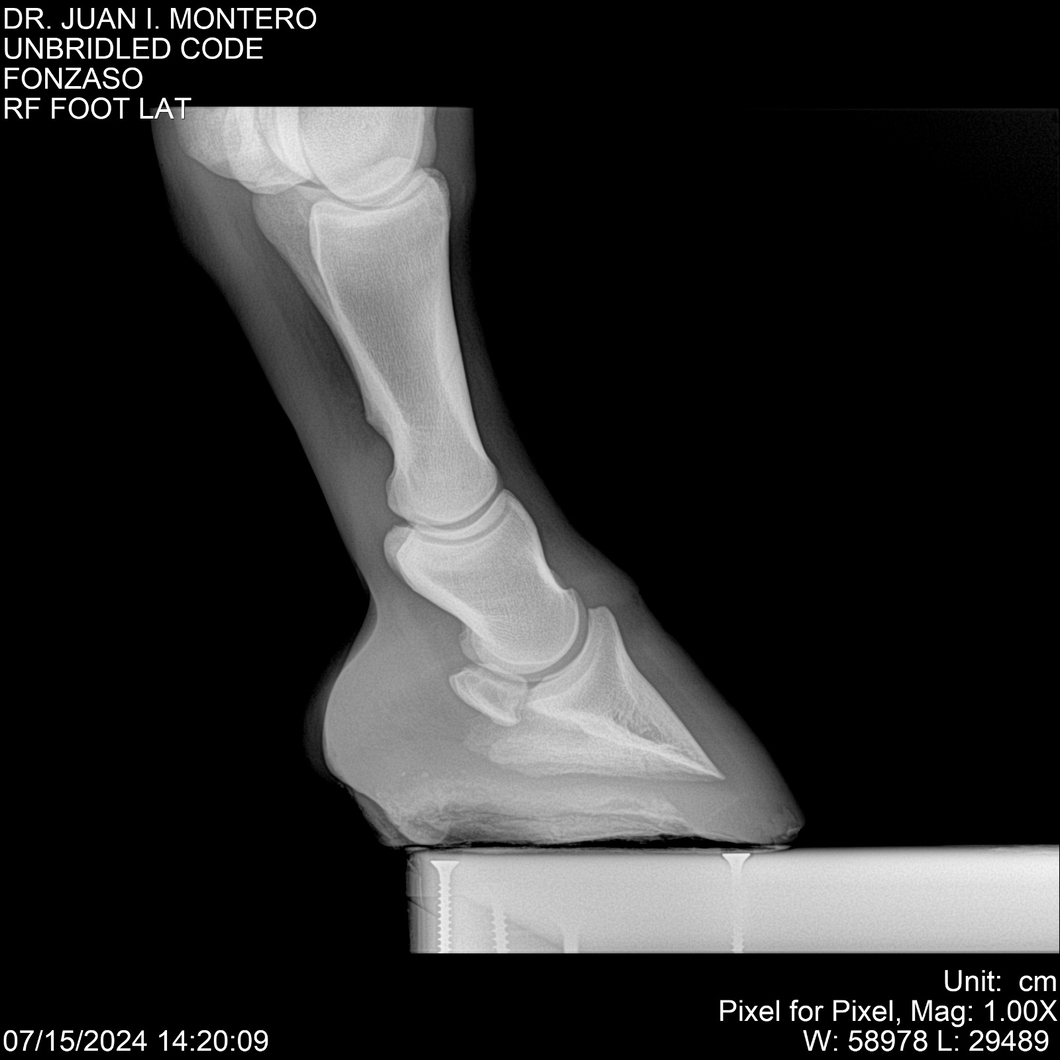

• Empresa: Abelenda N. R., Walter Hugo